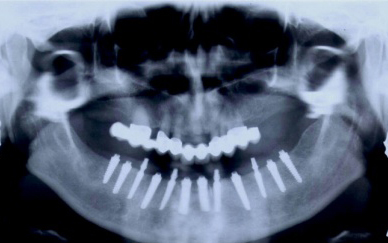

V případě chybění většího počtu zubů v postranních úsecích čelistí je možné ošetření pomocí implantátů, které nahradí ošetření pomocí snímacích náhrad kotvených na zbývajících zubech nebo patře.

Podmínkou je opět dostatečné množství kosti.

Protetické řešení může být pomocí můstku, který je kotvený na implantátech nebo pomocí jednotlivých korunek na implantátech.

V zásadě je možné do těchto můstků zařadit i přirozené zuby, zejména pokud je potřeba tyto zuby ošetřit proteticky – korunkami. Korunky nebo můstky mohou být na implantáty nacementovány nebo přišroubovány.

Zdravé zuby zůstanou zachovány a přitom náhrady jsou pevné, jako na vlastních zubech